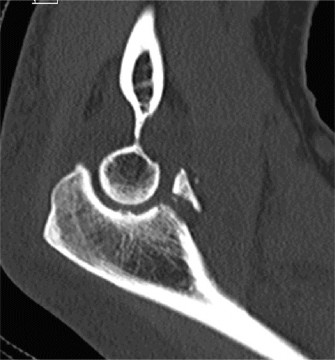

CT arthrograms of the patient’s left shoulder are shown in Figure 2–56. CRP is <3, ESR 45. The patient continues to have pain, so you decide to perform arthroscopic biopsy to obtain tissue cultures. Frozen sections show <5 PMNs per hpf, and Gram stains are all negative.

Figure 2–56

The correct answer is (B). Figure shows contrast under the glenoid component. Given the patient’s normal inflammatory markers and frozen sections combined with continued pain and loosening on CT, infection with P. acnes(an organism that is very difficult to isolate) should be investigated by holding any cultures for at least 2 weeks to see if it will eventually grow. Chocolate agar (Choice C) is mainly used for growing species such as H. influenzae and Neisseria meningitidis not P. acnes. A is incorrect since the patient’s cell count and frozen sections are clearly abnormal, therefore referral to pain clinic would not be appropriate. However, Choice D would be too aggressive an approach given that no organisms have been isolated, frozen sections show <5 PMNs per hpf, and the patient has relatively normal inflammatory markers.